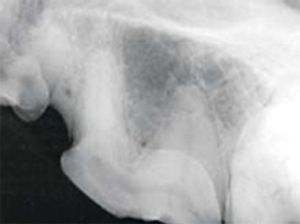

Oronasal and oroantral fistulas are communications between the oral cavity and the respiratory tract.